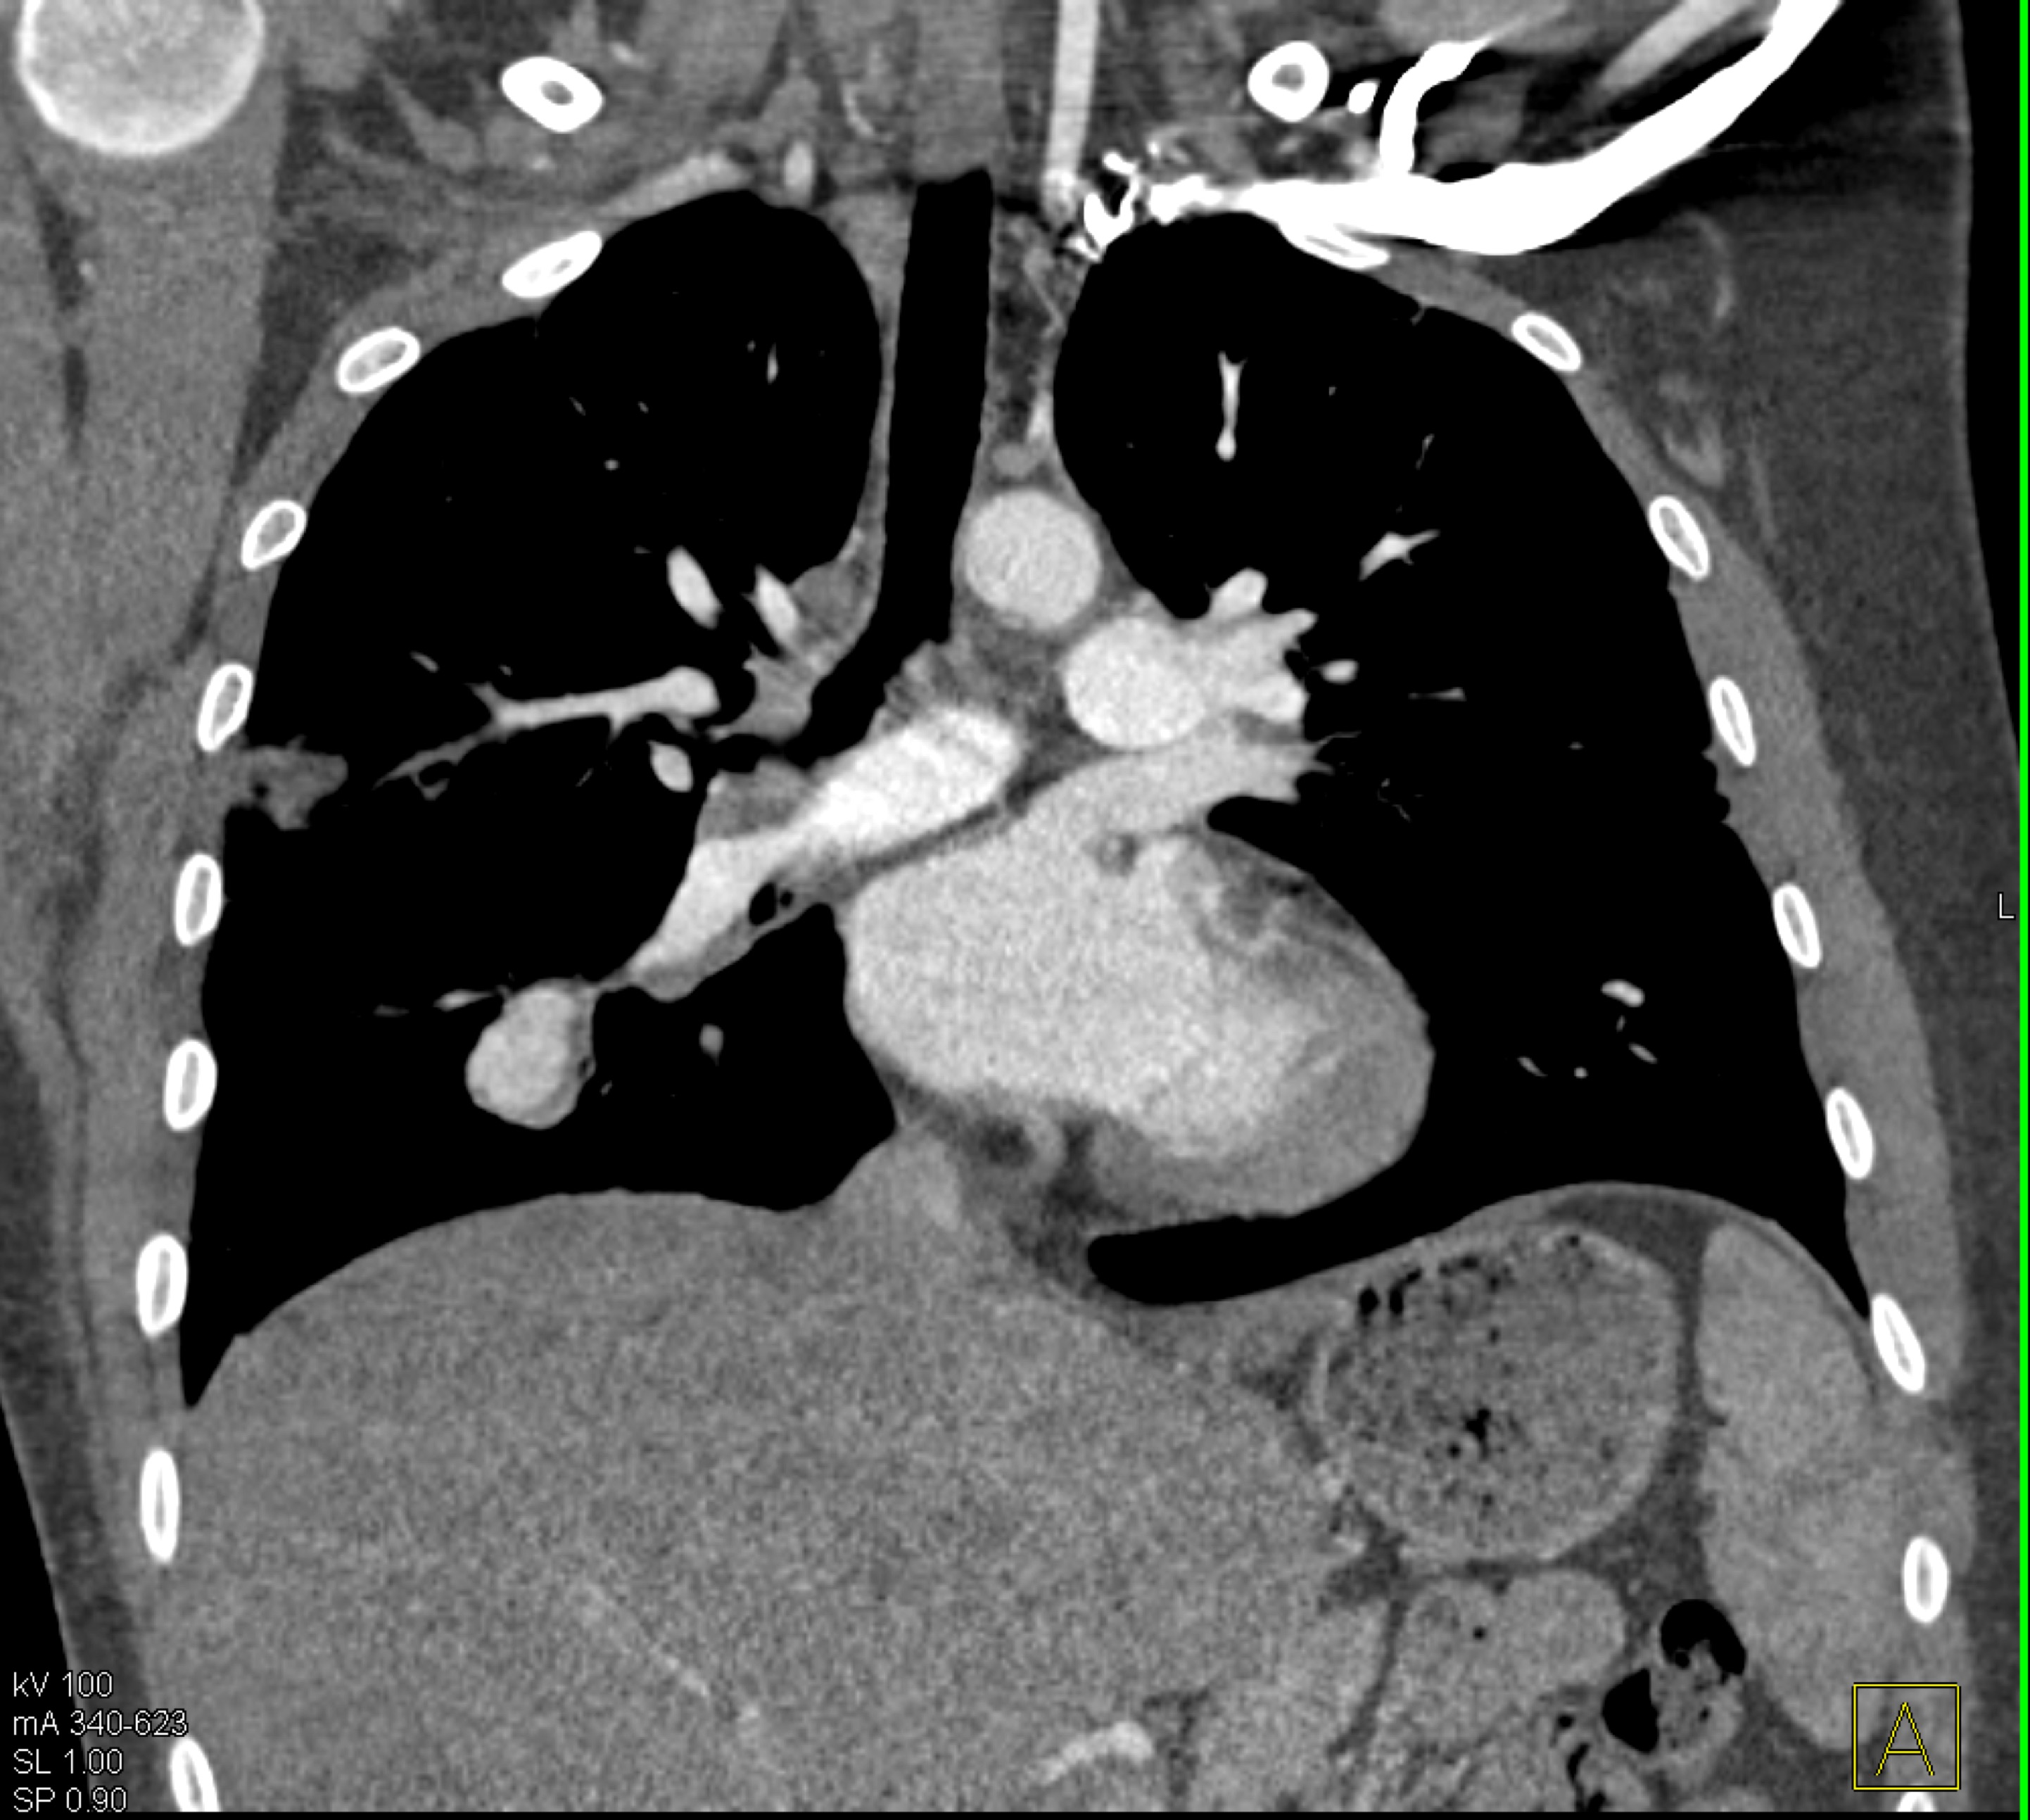

8) In this patient with mediastinal widening on CXR the best diagnosis is?

lymphoma

germ cell tumor

lung cancer

teratoma